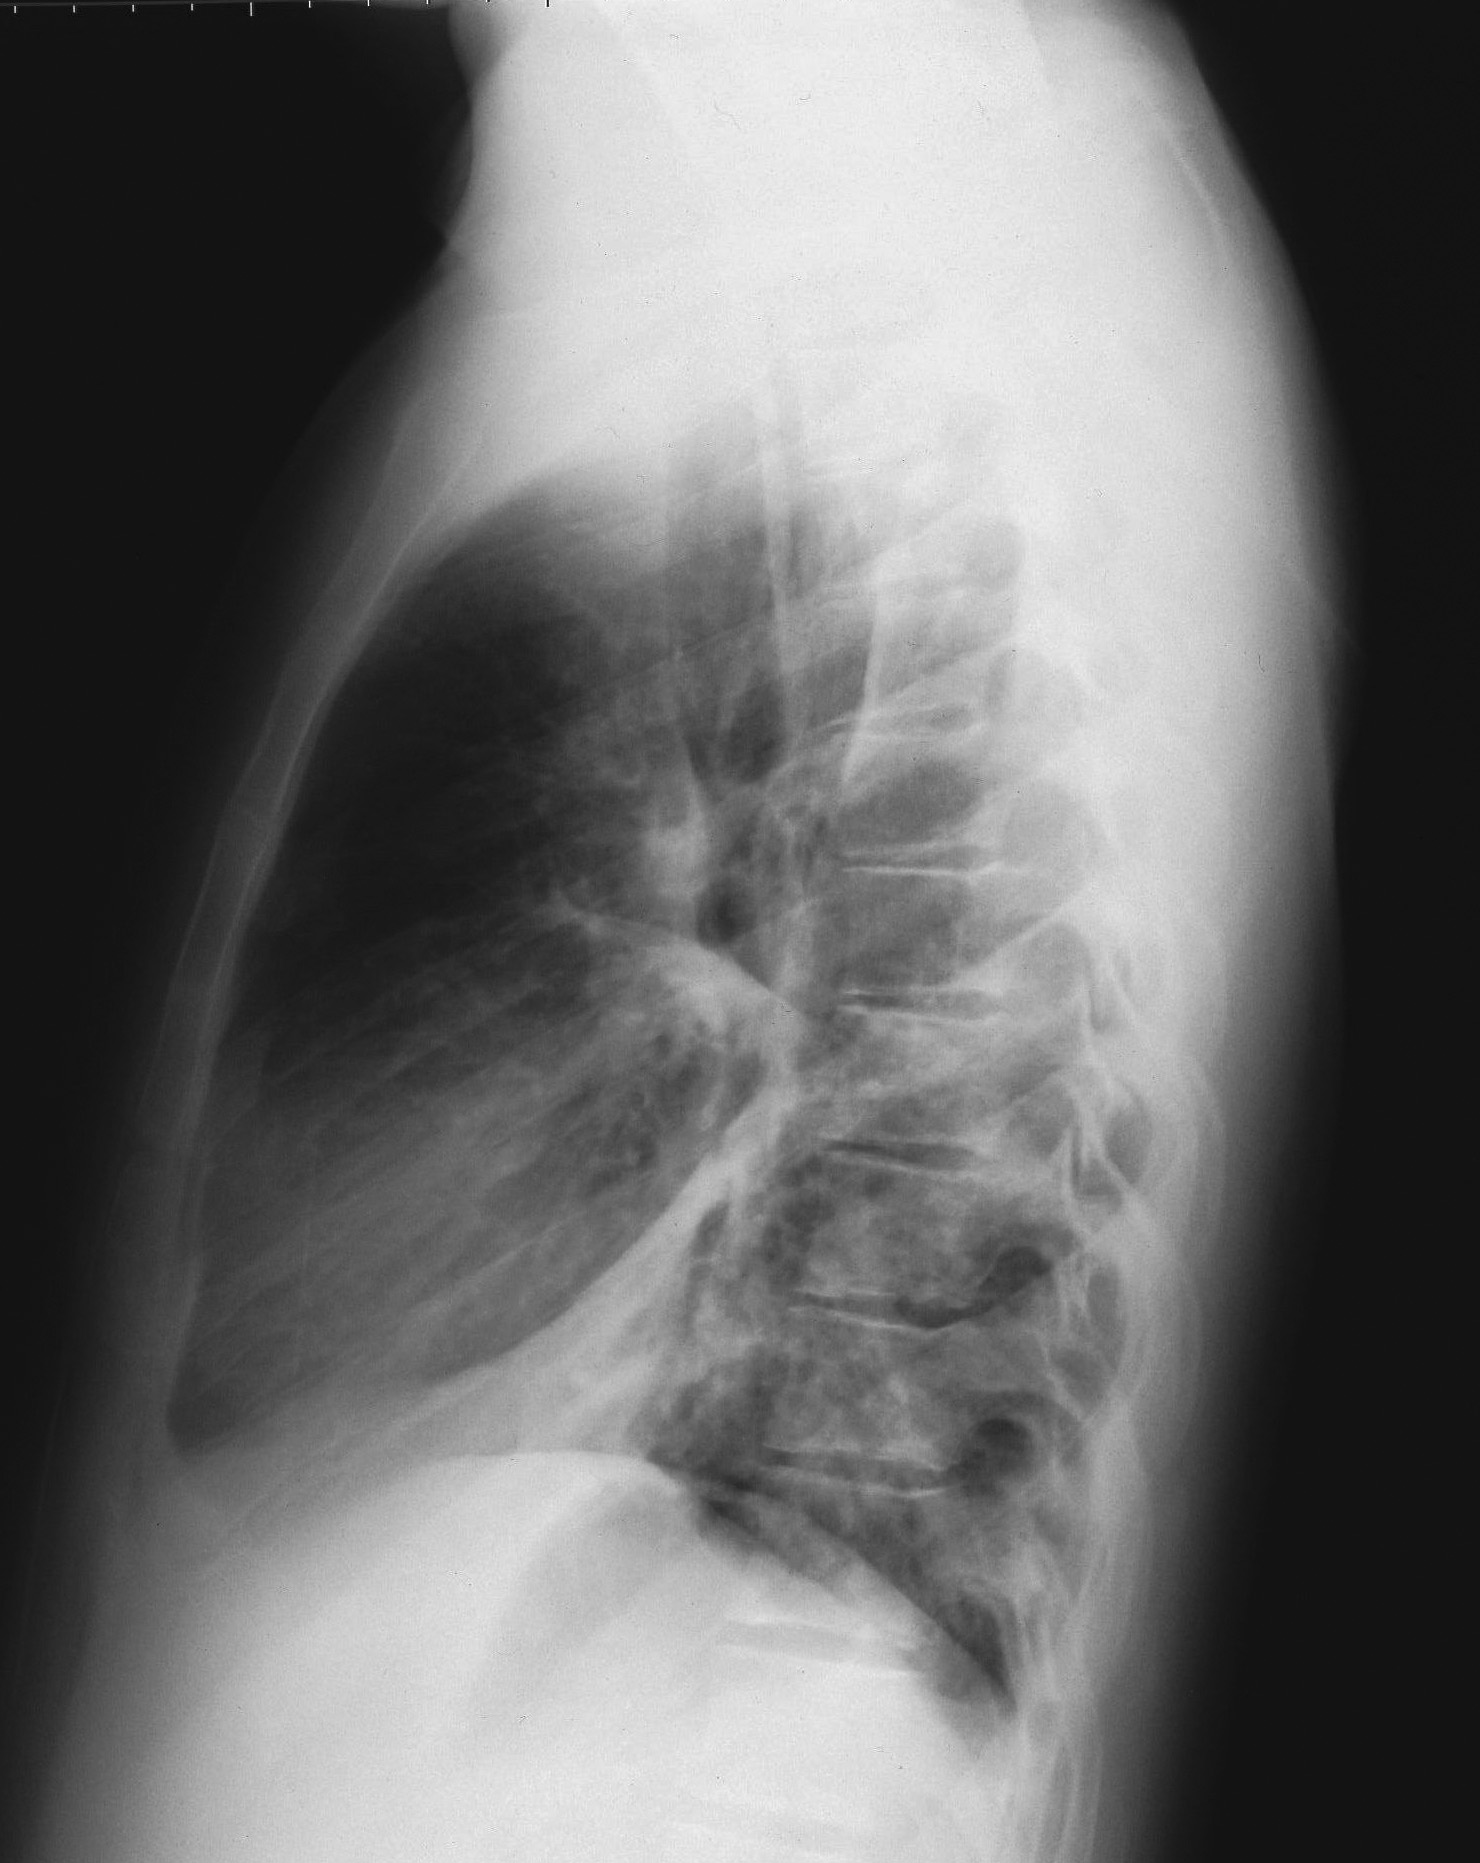

Nel complesso, cinque pazienti hanno presentato gastro-enterite con severa disidratazione, quattro bronco-polmonite con crisi dispnoiche, due bronco-ostruzione con crisi di cianosi, uno impetiginizzazione delle lesioni cutanee e, infine, un paziente congiuntivite purulenta. I pazienti italiani hanno presentato una maggiore percentuale di complicanze rispetto ai pazienti rom (Figura 2). Tra i pazienti italiani, due hanno presentato gastro-enterite mentre tre hanno sviluppato una broncopolmonite, confermata dalla radiografia del torace (Figura 3). Il bambino di un mese è stato trattato con immunoglobuline e.v. Nessun paziente ha presentato complicanze neurologiche.

Figura 3a.

Figura 3b.

Figura 3. Radiogramma del torace in proiezione antero-posteriore (a) e latero-laterale (b) in un paziente italiano di 15.3 anni. È evidente una polmonite interstiziale bilaterale, più accentuata a dx, con obliterazione dello spazio retrocardiaco, diagnosticata dopo 2 giorni dalla comparsa dell'esantema.